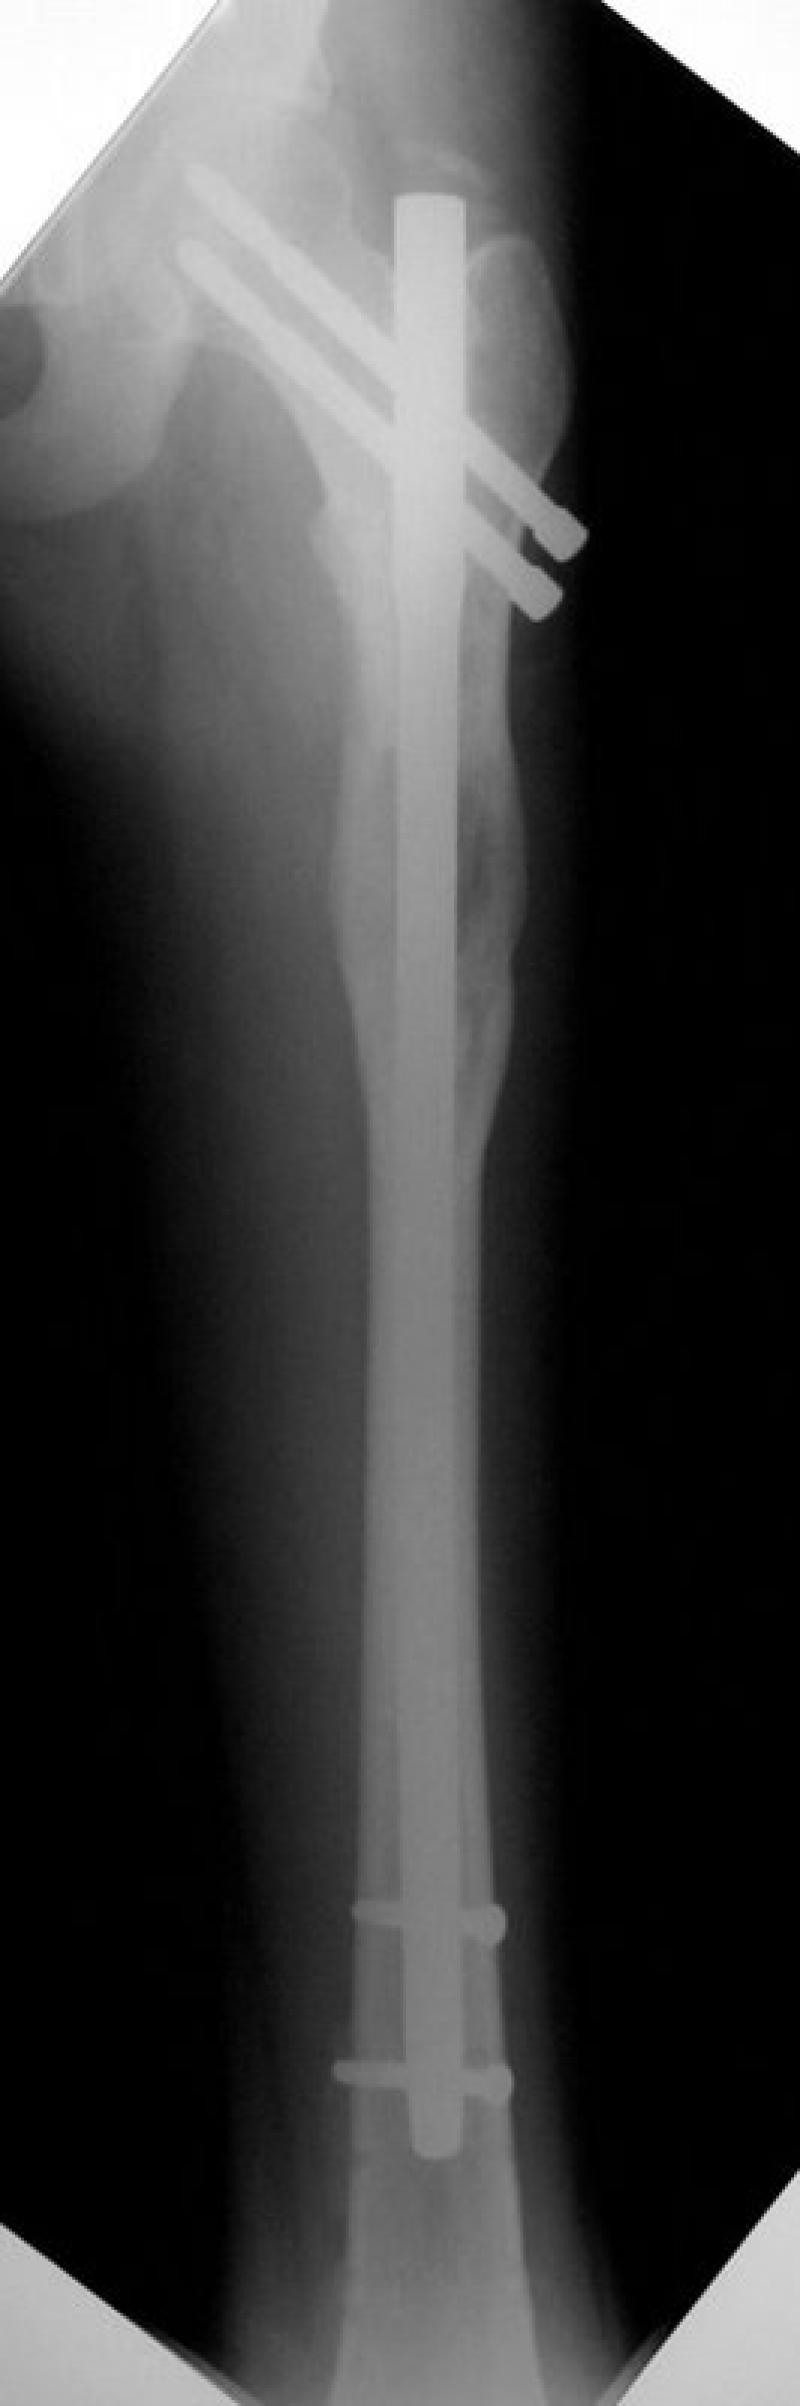

Combined Lengthening Technique (LON: Lengthening Over Nails)

The device is placed both within the bone and outside of the leg and lengthening process is performed for 2 -3 months in average. The part on the outside of the leg is removed after 3 months. Intramedullary nail within the bone can be removed with an additional operation after the bone is mended fully, if it is wished for. 6 - 7 cm of lengthening is achieved with a single session. If the process is applied for both lower and upper leg, 10 - 14 cm of lengthening is possible with one session.